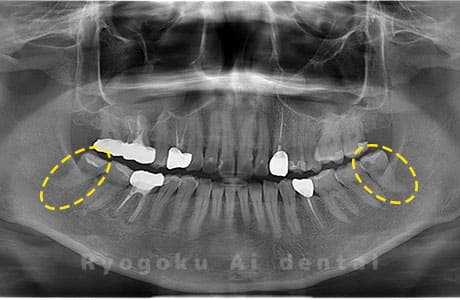

Case03

- 原因

- 上顎、下顎の親知らず

- 治療内容

- 上下4本の親知らずを抜歯したケースです。

<リスク・副作用>

手術後は痛み、腫れ、痺れなどの副作用が生じる場合があります。